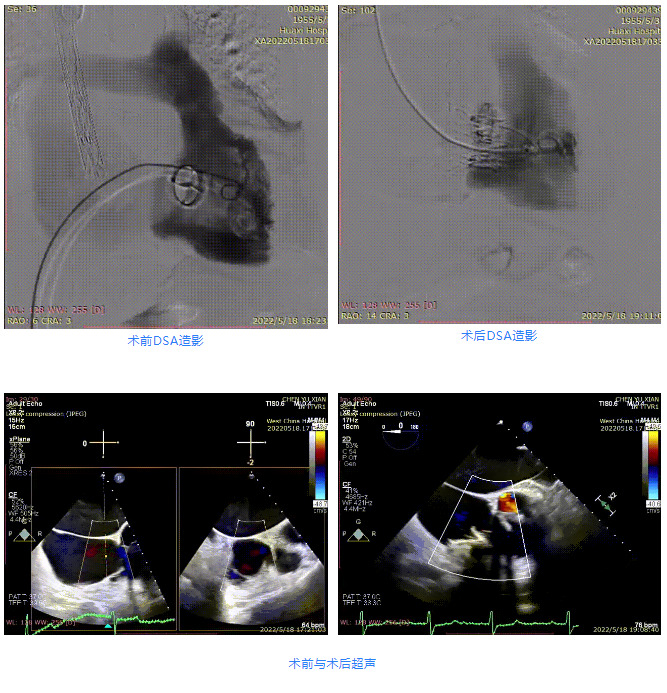

患者為67歲女性,主訴“活動后心悸、心累5年余”,偶有雙下肢水腫,無頭暈、暈厥史。20余年前,患者于本院行二尖瓣機(jī)械瓣置換術(shù),有高血壓和糖尿病病史,心功能Ⅲ級。術(shù)前超聲報告顯示,全心增大,左房為著,三尖瓣大量反流Vmax=2.5m/s,PG=24 mmHg,三尖瓣瓣膜稍增厚,回聲稍增強(qiáng);術(shù)前CT評估顯示,瓣環(huán)大小為41.4mm,瓣環(huán)平面與室間隔夾角為104°。

根據(jù)術(shù)前評估結(jié)果,郭應(yīng)強(qiáng)教授團(tuán)隊為患者量身定制了手術(shù)策略,決定使用LuX-Valve Plus經(jīng)血管三尖瓣置換系統(tǒng)開展手術(shù)治療。手術(shù)在全麻下進(jìn)行,采用經(jīng)右側(cè)頸靜脈入路,在經(jīng)食道超聲和DSA的指引下調(diào)整輸送器角度以達(dá)到正確位置,勾住前瓣后逐步釋放盤片,盤片打開后順利扎針,最終完成瓣膜植入,輸送器撤出。術(shù)后超聲提示人工三尖瓣同軸性良好,瓣架固定牢靠,無反流和瓣周漏,術(shù)后三尖瓣平均跨瓣壓差為1 mmHg。